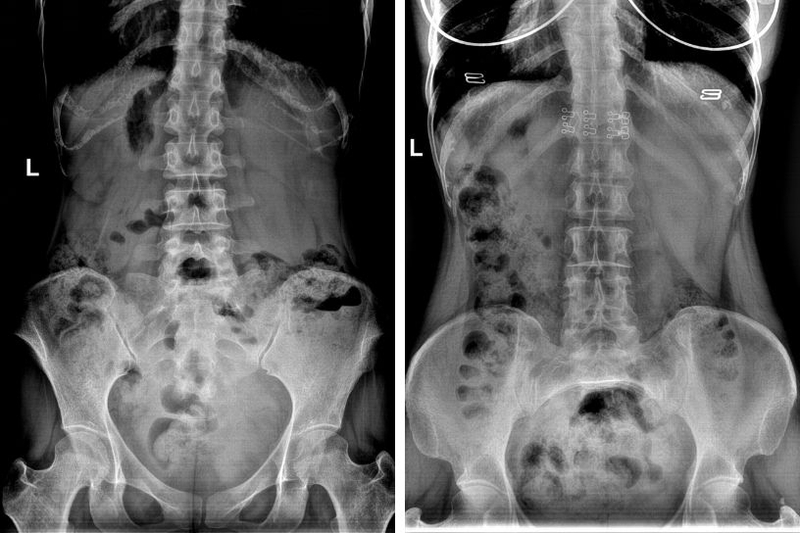

Chụp X quang bụng không chuẩn bị, còn được gọi là "chụp X quang bụng đứng" là một phương pháp chẩn đoán hình ảnh trong y học, sử dụng tia X đi qua cơ thể để cho ra hình ảnh của các cơ quan và cấu trúc trong vùng bụng, bao gồm dạ dày, ruột, niệu quản, túi mật, gan, vùng thận và phần dưới của phổi.

Chụp X quang bụng không chuẩn bị là một phương pháp hữu ích trong việc chẩn đoán và xác định nhiều loại bệnh liên quan đến vùng bụng. Nó có thể phát hiện các vấn đề như sỏi thận, sỏi mật, tắc ruột, viêm tụy, có khí tự do ổ bụng, các dị vật cản quang và nhiều vấn đề khác liên quan đến các cơ quan và cấu trúc trong vùng bụng.